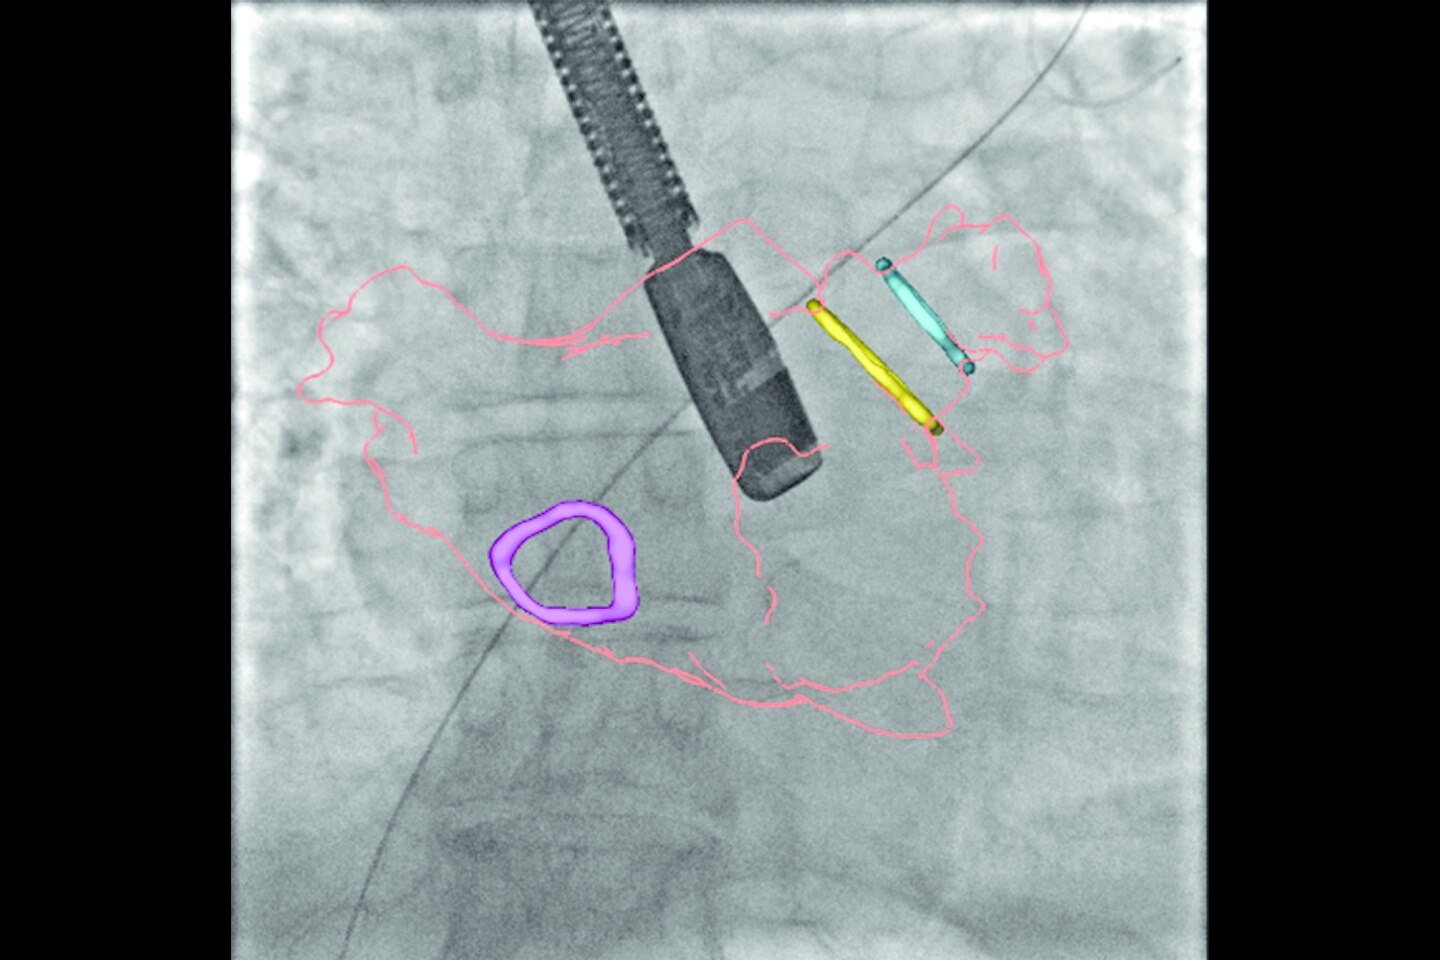

Interface ouverte

Grâce à une plateforme ouverte, l'OEC 3D s'intègre parfaitement aux systèmes de navigation et de robotique. La fonctionnalité OEC Open permet d'exporter un ensemble de données 3D haute-résolution vers des systèmes acceptant les images DICOM.

Un arceau 3D qui s'adapte à votre routine: de l'arthrodèse à la fracture, en passant par l'angiographie et le placement de stents